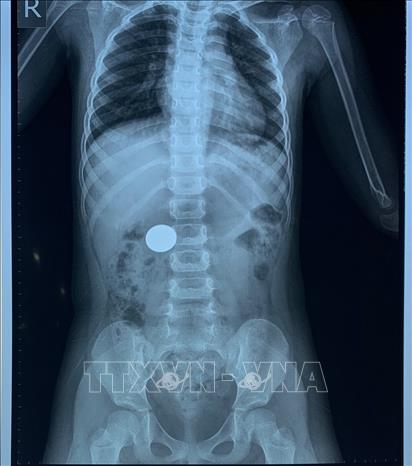

Trong ảnh: Phim chụp phát hiện đồng xu trong cơ thể bé gái 4 tuổi do nuốt phải trong lúc chơi đùa. Ảnh: TTXVN phát

Chiều 15/12/2020, Bệnh viện Hoàn Mỹ Đà Nẵng vừa nội soi can thiệp cấp cứu thành công, gắp được dị vật là một đồng xu nằm ở dạ dày của bệnh nhân nhi 4 tuổi do nuốt phải trong lúc chơi đùa. Hiện sức khỏe bệnh nhi đã hồi phục bình thường. Ảnh: TTXVN phát